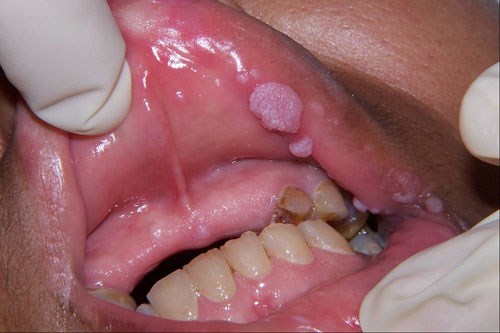

![]() Sùi mào gà là một trong số 8 căn bệnh lây nhiễm qua đường tình dục, mức độ nguy hại của nó đối với sức khỏe con người không thể coi nhẹ. Sùi mào gà là bệnh lây truyền qua đường tình dục do nhiễm HPV, biểu hiện bằng các sẩn sùi mềm ở sinh dục ngoài có khi ở hậu môn hoặc vùng da khác như ở miệng. Tác nhân gây bệnh là HPV (human papiloma virus), thuộc loại papova virus có DNA. Chủ yếu lây truyền qua đường tình dục, còn có thể lây truyền qua tiếp xúc. Trẻ sơ sinh có thể bị lây bệnh từ người mẹ mắc bệnh trong lúc sinh đẻ. |